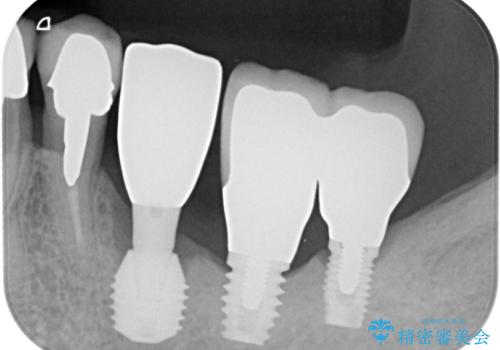

そのため、当院に新しく導入した手法により、抜歯をした日にインプラントを埋入し、そのままを仮歯を装着することで、他の歯への負担を軽減する計画を立てました。

インプラント埋入時に植立具合の安定性を測定したところ、十分な数値が得られたため、速やかに仮歯を装着して咬合回復をさせることができました。

抜歯を含めた外科処置を1回に抑えることができ、あっという間に治療を終えることができました。